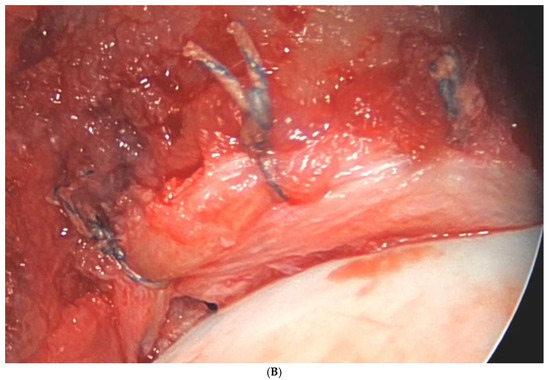

| Della Rocca F et al. [42] | Endoscopic gluteus medius repair combined with systematic gluteus maximus tendon re-lease leads to high patient satisfaction. |

- Della Rocca, F.; Di Francia, V.; Giuffrida, A.; Rosolani, M.; D’Ambrosi, R.; D’Addona, A. Satisfactory results after endoscopic gluteus medius repair combined with selective gluteus maximus reflected tendon release for the treatment of a full-thickness tear of gluteus medius. Knee Surg. Sports Traumatol. Arthrosc. 2023, 31, 2038–2045. [Google Scholar] [CrossRef] [PubMed]